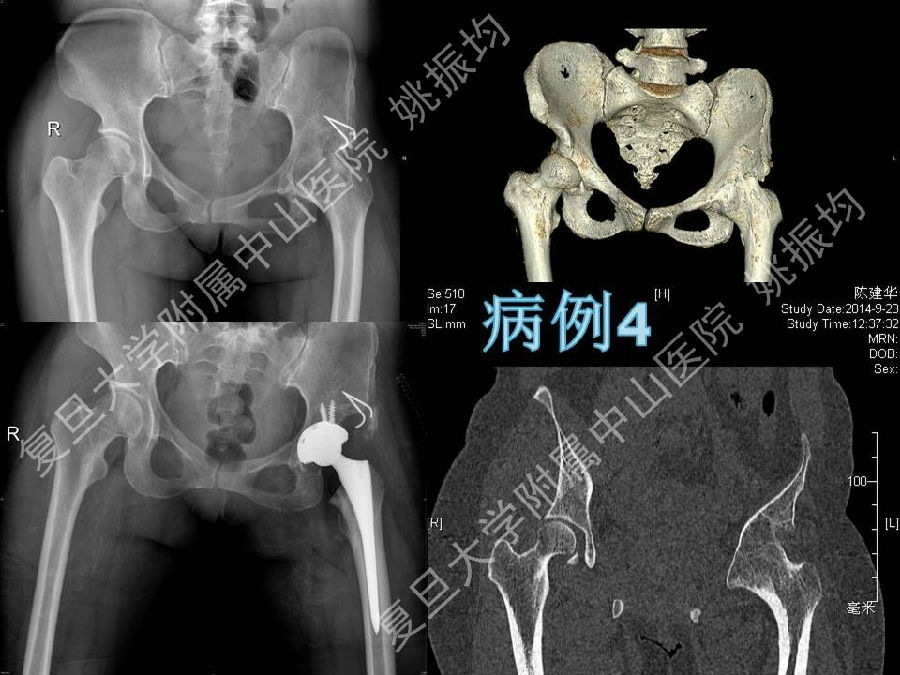

强直性脊柱炎(ankylosing spondylitis, AS)是一种血清学阴性的慢性进行性炎症性疾病,主要侵犯骶髂关节、脊柱和髋关节等。对AS晚期引起的髋关节畸形施行全髋关节置换术,是目前公认的改善关节功能的有效方法.

复旦大学附属中山医院姚振均教授在“强直髋关节的人工关节置换”专题授课中从强直性脊柱炎的患者选择、术前准备、手术技巧、术后护理、病情转归、典型病例分享方面,讲述了他是如何做强制髋关节置换手术的,我们一起来回顾下精彩课件吧!